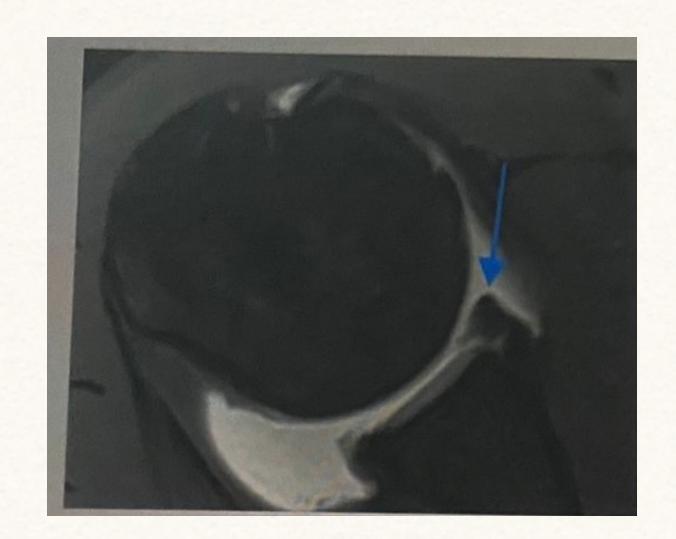

18-year-old male presented after sport injury and unable to do internal rotation of right shoulder. What is the name of the injury seen in the figure?

- Hill-Sachโs defect

- Hill-Sachs lesion

A case scenario about a male with anterior shoulder dislocation. What does the figure 1b show?

reverse - Hill sachs lesion

What do you see in this image?

- Hill sachs lesion